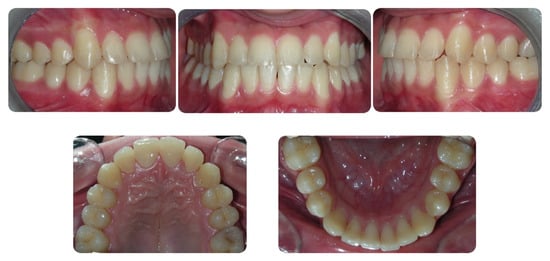

2.5. Results